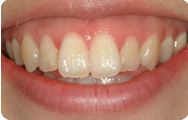

치아교정 레진브라켓 전후사례 | 2020.03.06 |